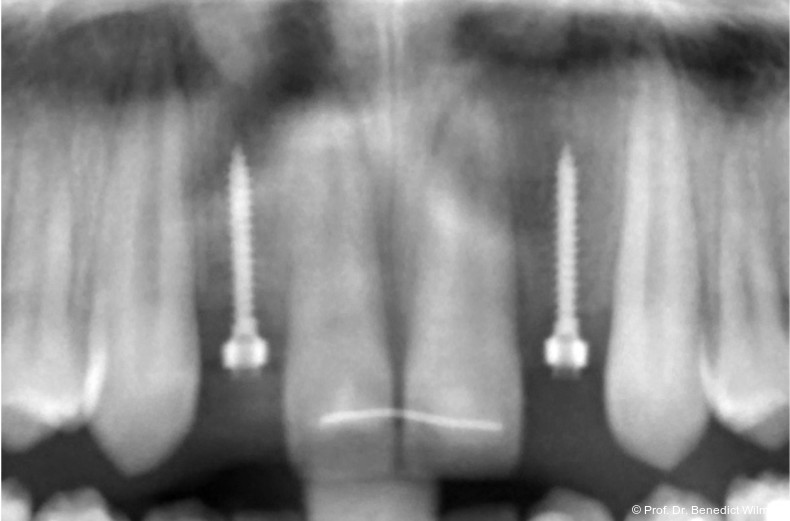

Bei einer elfjährigen Patientin fehlten bei Zustand nach Frontzahntrauma im Alter von neun Jahren beide oberen mittleren Schneidezähne (Abb. 8a+b). Als temporärer Ersatz wurden Miniimplantate (Abb. 9, 2 x 13 mm) eingesetzt und Kronen im Labor angefertigt, welche auf den Miniimplantaten verschraubt wurden (Abb. 10a+b). Die Miniimplantate wurden im Alter von 19 Jahren, also nach achtjähriger Nutzung (Abb. 11a+b), durch dentale Implantate ersetzt.